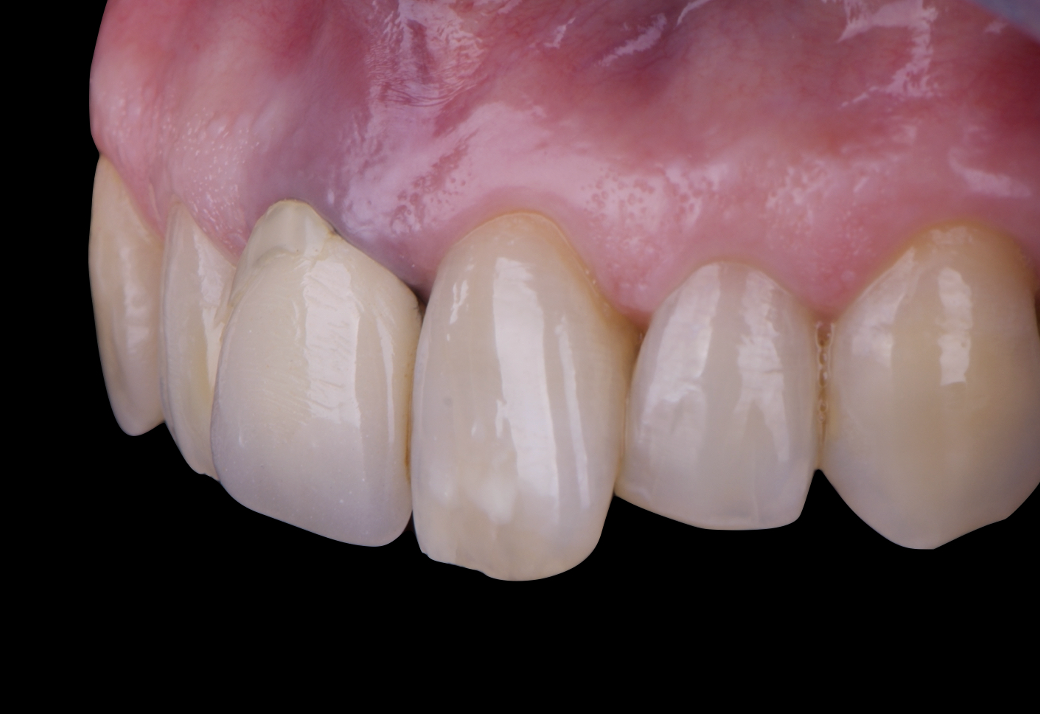

After an appropriate healing period, the definitive prosthesis was planned and delivered. A screw-retained zirconia crown was fabricated to ensure long-term durability, optimal esthetics, and retrievability. Zirconia was selected for its mechanical strength and excellent esthetic properties, blending seamlessly with the adjacent natural dentition in both form and color.

The final crown was designed to maintain the gingival architecture that had been shaped by the provisional. Special attention was paid to the emergence profile, contact points, and translucency to achieve harmony with the patient’s smile. The definitive restoration provided functional stability and esthetic integration, fulfilling the patient’s expectations for a fixed and natural solution.